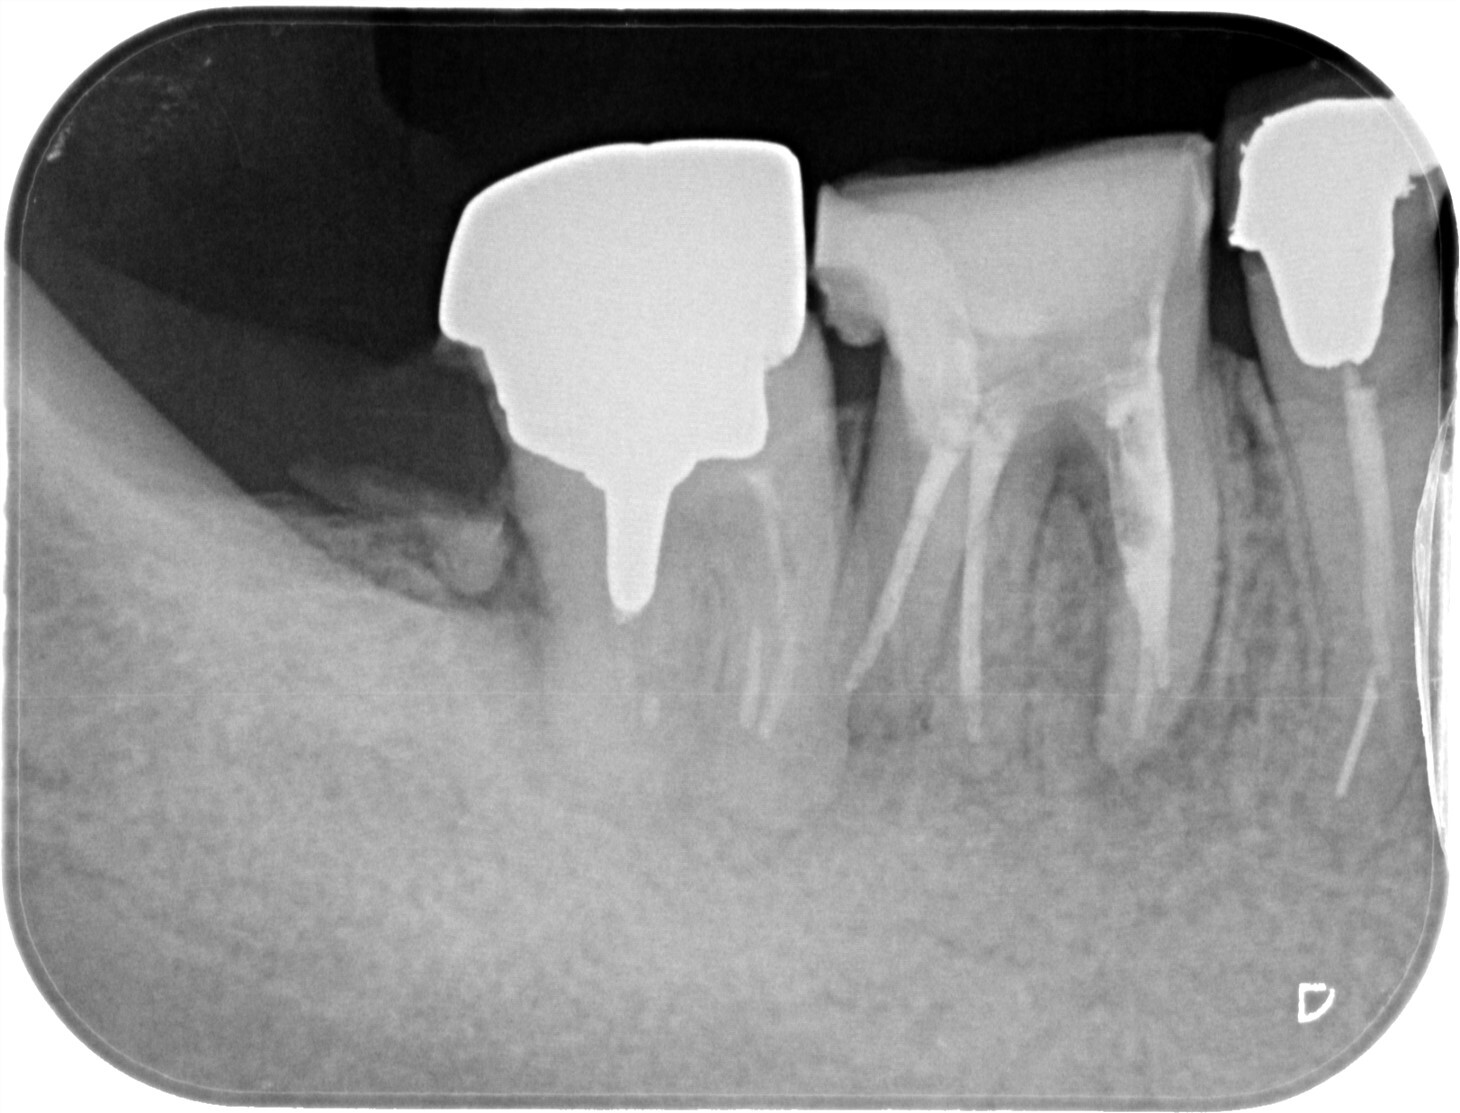

| 主訴 | 過去の治療にて根管充填後、噛むと違和感・痛みが出てきた。一度詰めた薬を撤去してもらったが症状が変わらなかったため来院。 |

| 治療内容 | ラバーダム防湿を行い、マイクロスコープにて根尖部の溢出ガッタパーチャの除去を行いました。 |

| 想定されたリスク | ガッタパーチャが取り切れない可能性がある。除去したとしても違和感・痛みが続くこともある。 ガッタパーチャを取ることにより根尖が過拡大されてしまい、根管充填時に更なる溢出を起こす可能性がある。 MTAセメント根充や外科的な処置が必要となる可能性がある。 |

CT撮影により根尖部にガッタパーチャの溢出を確認。

拡大視野下にて残存ガッタパーチャを確認しながら過拡大に注意しながら除去。

その後根管充填を行った症例です。ガッタパーチャ除去したことで症状が改善されました。